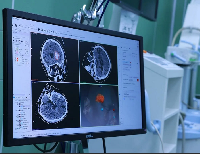

Магнитно-резонансная томография (МРТ):один из самых эффективных методов диагностики заболеваний